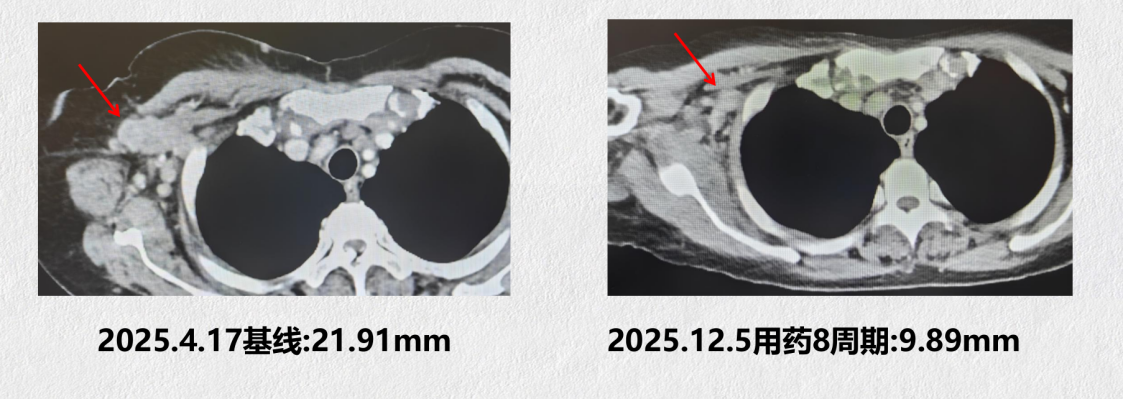

2025年12月5日完成8周期疗效评估,乳腺病灶进一步缩小至21.69 mm,锁骨上淋巴结缩小至13.56 mm,右腋窝淋巴结缩小至9.89 mm,肺部两处转移灶分别进一步缩小至13.82 mm和8.27 mm;胸骨骨转移灶影像学评估维持PR状态。疗效评价为维持PR,未见进展事件

图2:腋窝淋巴结治疗前后变化

2025年6月19日完成2周期疗效评估,与2025年4月17日基线影像相比,各靶病灶均出现不同程度缩小:乳腺原发病灶由34.34 mm缩小至28.44 mm,锁骨上淋巴结由36.05 mm缩小至27.20 mm,右腋窝淋巴结由21.91 mm缩小至17.69 mm,两处肺部转移灶分别由22.73 mm和19.03 mm缩小至15.44 mm和12.35 mm。疗效评价为部分缓解(PR)